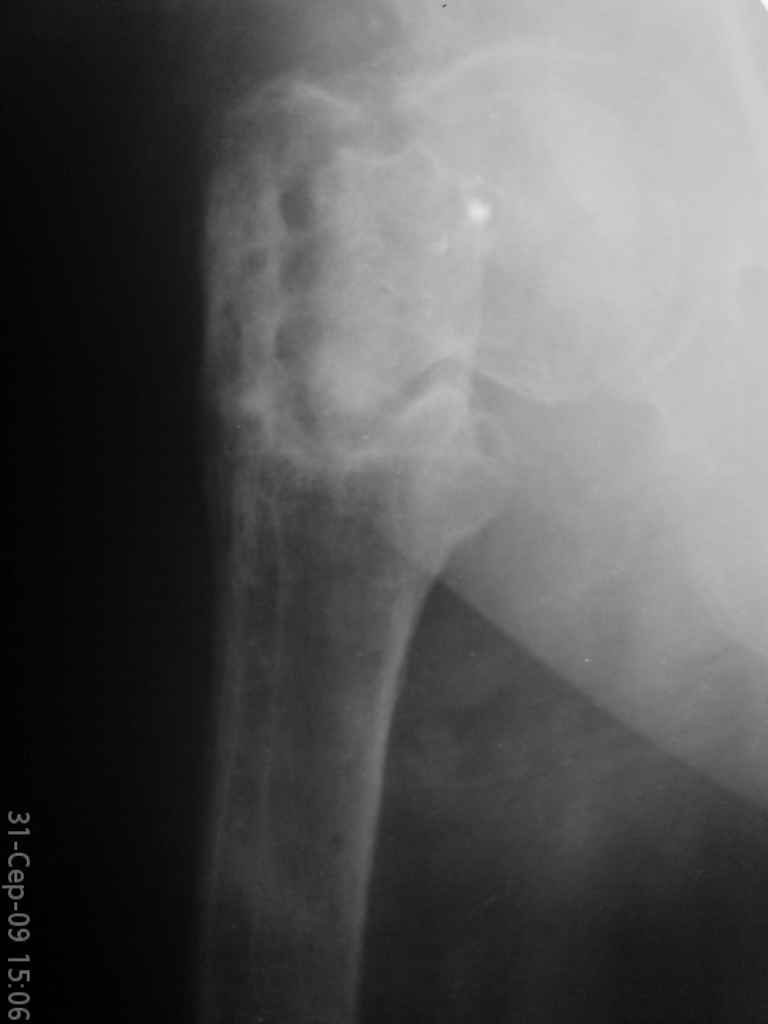

Уважаемые коллеги, помогите определиться с тактикой лечения. Больная, 62 года,жалуется на боли,неопорность левой ноги. Ходит с помощью костылей, укорочение ноги 3 см. Два года назад была оперирована кокой-то накостной пластиной, пластину удалили 4 мес назад. Вопрос такой: предлагать эндопротезирование или делать МОС (что-то по типу стержня Gamma)?За качество снимков извините, по данным МРТ - головка живая

На прошлой неделе оперировали похожего пациента. 2 года после неудачного остеосинтеза PFN в другом регионе. После удаления остатков железа выявилось несращение вертельной области.

В такой ситуации важно устранить варусную деформацию. При использовании гвоздя это непросто. Поэтому в число рассматриваемых

вариантов стоило бы включить вальгизирующую остеотомию с фиксацией 130-градусной клинковой пластиной или DHS.